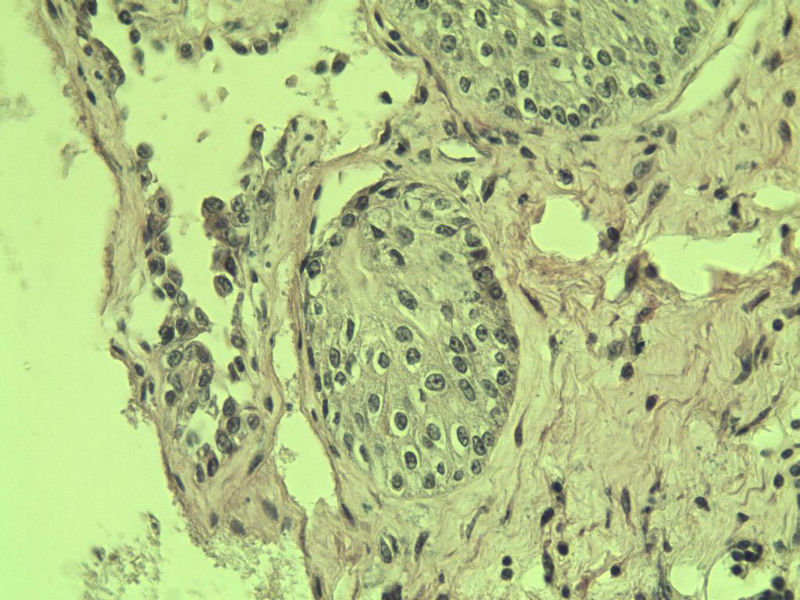

男 75岁 因排尿困难半年行前列腺切除术,体积 4 × 3 × 2.5 cm3,切面灰白,实性,质韧。请各位老师看看 有问题没? 谢谢了!

良性前列腺增生伴尿路上皮化生

呈巢上皮为尿道周围前列腺组织正常现象。尿路上皮-前列腺腺体过度。

前列腺增生伴尿路上皮鳞化及Brown巢形成,未见恶性。